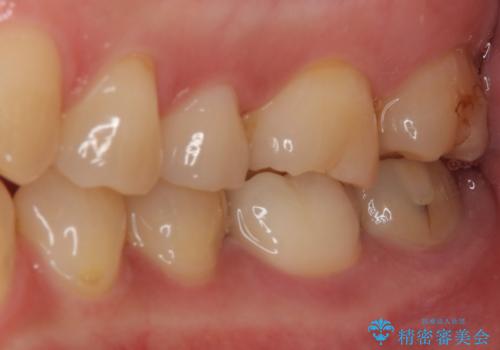

奥歯は虫歯が放置されていましたが、特に症状はなく歯髄の状態も正常でした。

前歯、奥歯ともにオールセラミッククラウンやセラミックインレーにて治療を行うこととしました。

前歯のセラミッククラウンは周りの歯と調和させるためにオーダーメイドタイプのものをおすすめしましたが、元が白すぎていたため、概ね色合いが合えば大丈夫であるとのことで、既製パターンの色調で仕上げました。